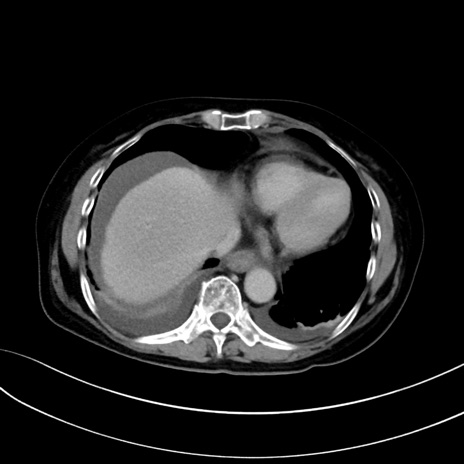

(冠状断像)1日半後